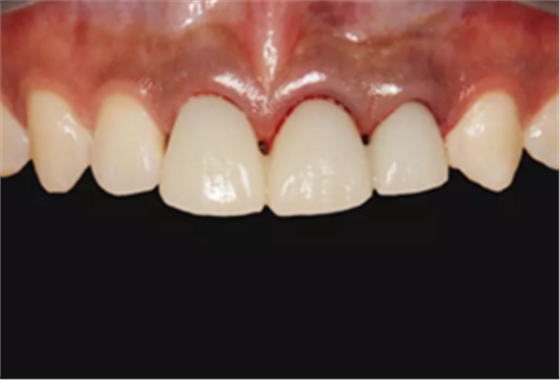

图2 术前口内像

图14 术后4个月口内像